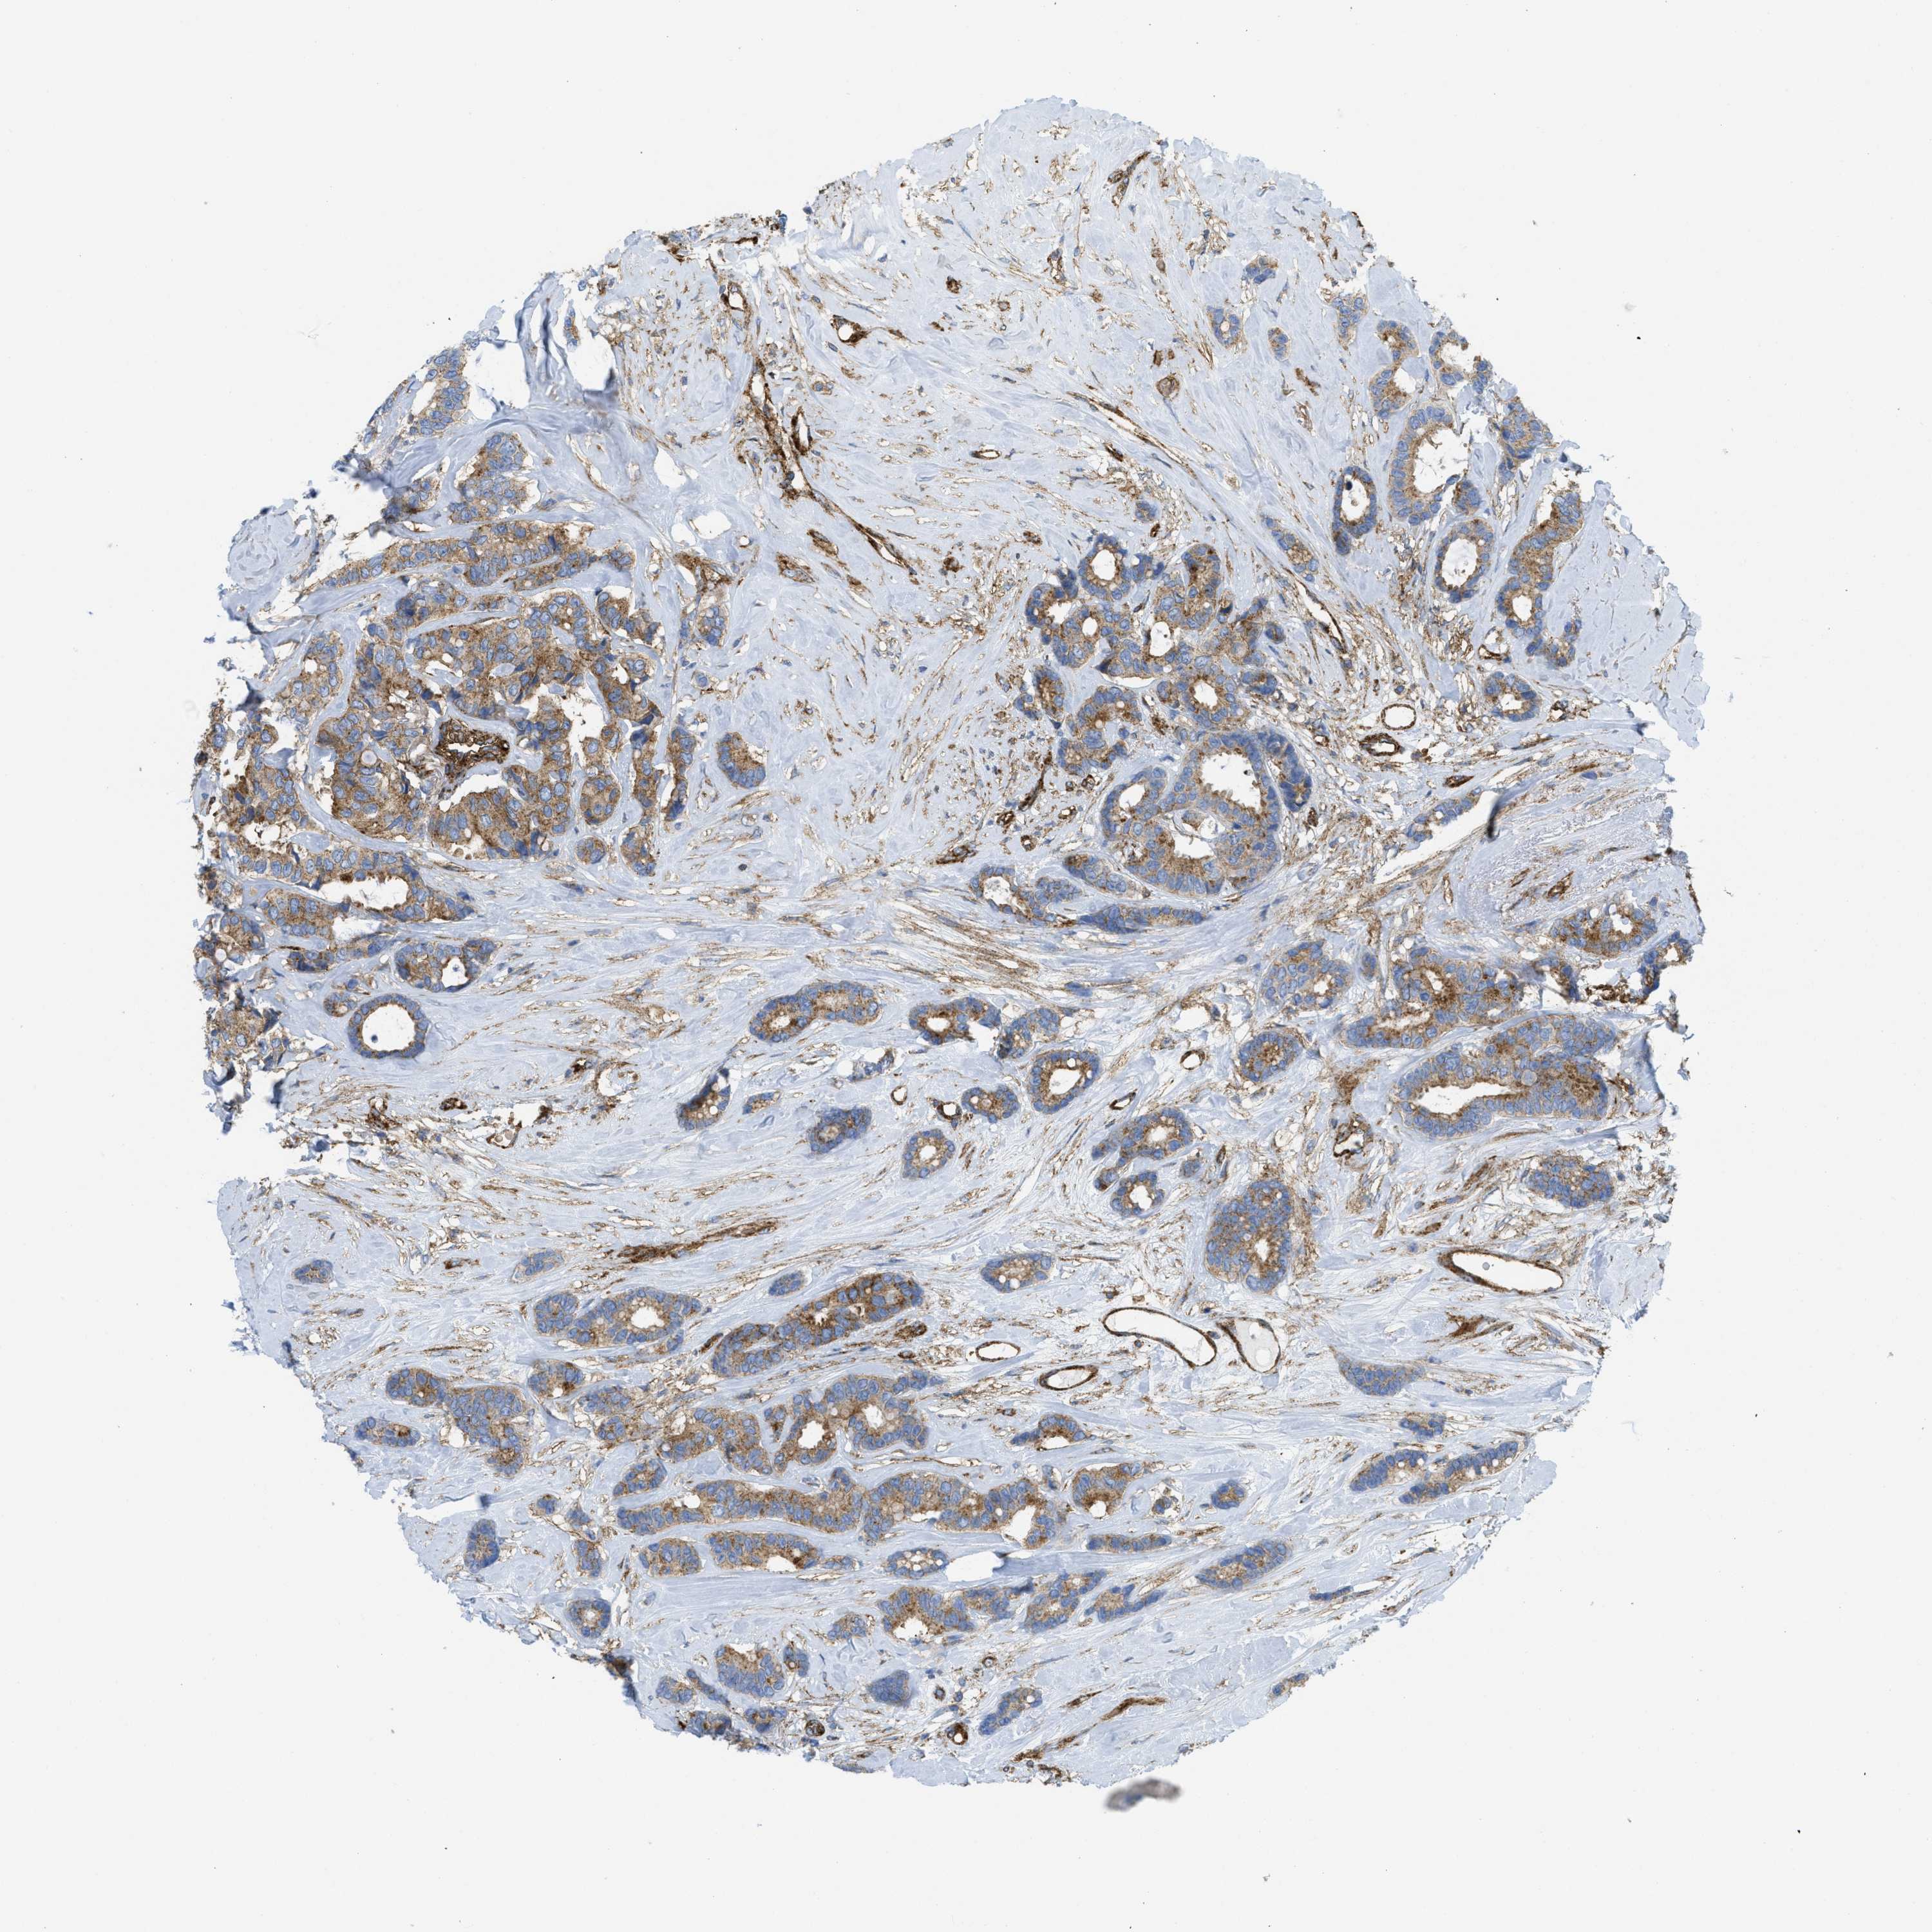

CANCER BREAST CANCER Show tissue menu

BRCA TCGA BRCA VALIDATION PROTEIN EXPRESSION